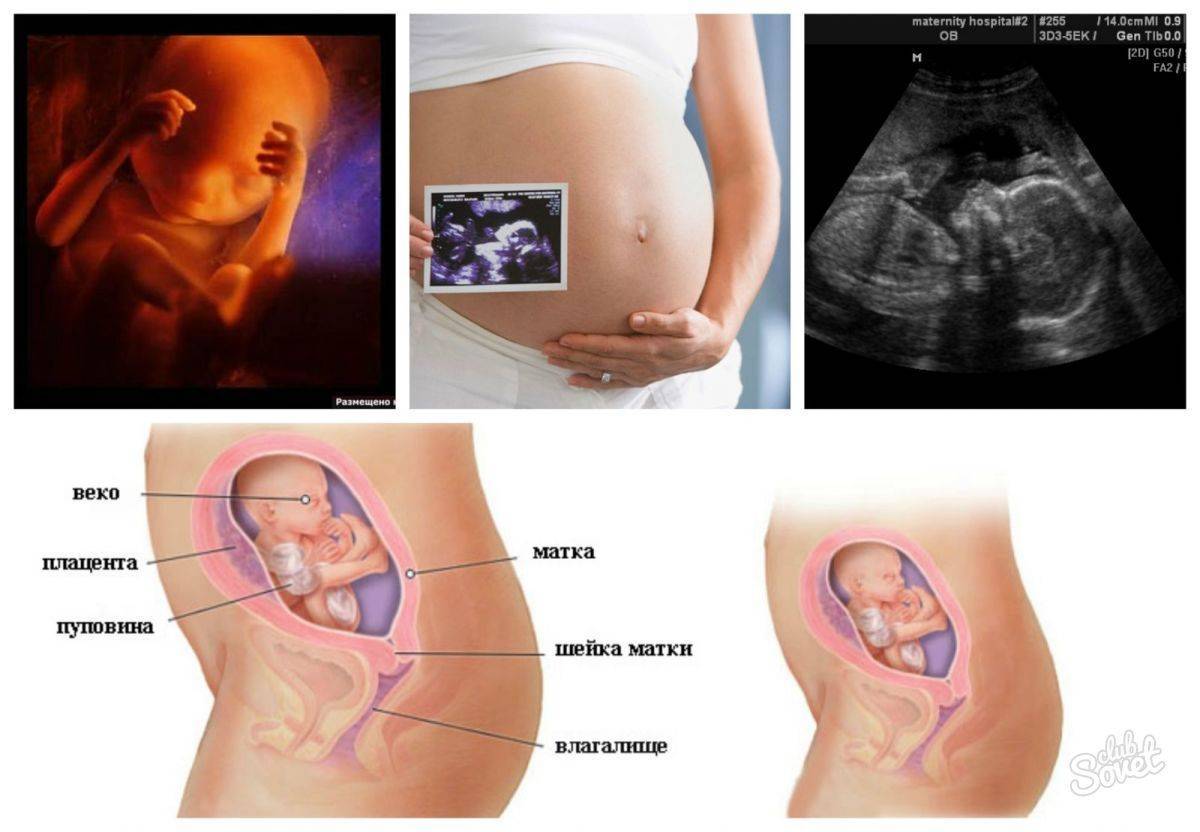

Что определяют на УЗИ

На 22-й неделе проводится второе скрининговое УЗИ, если оно не было назначено немного раньше. В отличие от первого скрининга, сейчас анализы крови не являются обязательными, если в прошлый раз не было выявлено риска рождения ребёнка с аномалиями развития. В ходе исследования врач определяет положение малыша в утробе. Оно может быть:

- тазовым;

- поперечным;

- головным.

На 22-й неделе на УЗИ хорошо просматриваются контуры тела малыша

Оптимальным вариантом является головное предлежание, когда малыш занимает позицию головой вниз и вверх ножками. Если он сидит на попе или лежит на боку, не нужно расстраиваться, ведь ещё есть время и место в полости матки, чтобы перевернуться

Однако специалисты обращают внимание на положение плода уже сейчас. А также доктор изучает развитие жизненно важных органов, частей тела малыша, оценивает его рост и массу, соответствие гестационному сроку развития

Нормальными считаются следующие показатели:

- БПР (бипариетальный размер, измеряемый от одного до другого виска головы) – 48–60 мм;

- ОГ (окружность головы) – 64–76 мм;

- ОЖ (окружность живота) – 148–190 мм.

Оценивается также состояние матки на предмет тонуса, состояние и расположение плаценты, степень её зрелости

Немаловажное значением имеет количество околоплодных вод

На 22-й неделе на УЗИ хорошо видно, кого ждёт женщина, конечно, при условии доступного для датчика расположения половых органов плода

22 неделя беременности при ЭКО — что делают врачи?

При ЭКО-беременности осмотр проводят каждые две недели. Во время приема врачи осматривают и определяют длину шейки матки. При необходимости проводится ультразвуковое исследование.

Если есть подозрения на патологию плода, назначается амниоцентез.

Все части лица уже хорошо сформированы. На глазках есть веки, которые приоткрываются. Выросли реснички и бровки, которые иногда хмурятся. Мимика ребенка пока не сознательна. Если сделать УЗИ в 22 недели, будет видно не только, что происходит с плодом, но и все его структуры лица. Причем, если малыш займет удобное для врача положение, уже можно будет понять, на кого из родителей он больше похож, чей у малыша рот или нос. На память можно будет сделать фото и видеозапись.

Фетометрия плода сейчас следующая:

На этом сроке уже проводят допплерометрию — то есть смотрят состояние кровотоков ребенка. Если есть нарушения — может потребоваться стационарное лечение. Иногда нарушения бывают критическими, и тогда определяется значительная задержка развития плода, гипоксия. Обычно симптомом этого является медленный рост обхвата живота и высоты дна матки, а также слабые и редкие шевеления ребенка.

Если показания допплера нормальные, плод развивается согласно своему гестационному возрасту, прогноз на течение беременности и родов благоприятный.

При допплерометрии оценивается кровоток в артериях пуповины. Эти показания являются важнейшими характеризующими маточно-плодово-плацентарного кровообращения.

Кроме допплерометрии, на УЗИ в двадцать две недели гестации смотрят структуру плаценты. Она должна иметь однородную структуру. Возможно небольшое расширение межворсинчатых пространств. Данная особенность характерна для женщин, у которых часто бывает пониженным артериальное давление. Степень зрелости плаценты пока нулевая. Если врач ставит уже первую, это означает, что есть риск развития фетоплацентарной недостаточности, внутриутробной задержки развития плода. И, возможно, потребуется сделать перед третьим скрининговым УЗИ еще одно, контрольное, чтобы оценить кровотоки плода.